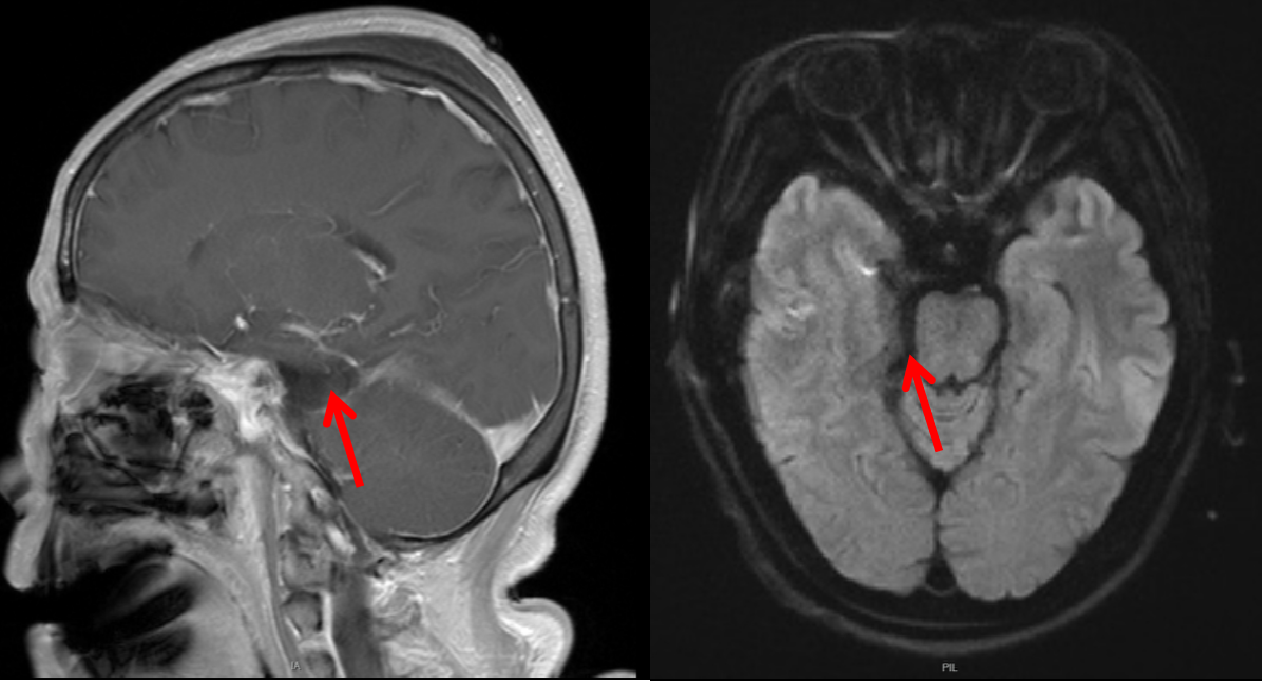

(见下图,左侧为术前,右侧为术后)

术前磁共振MRI增强显示岩斜区病变,后颅窝病变累及面神经水平,我们沿用改良扩大乙状窦后入路,在显微镜下行乙状窦后经天幕入路,术后1天磁共振复查显示肿瘤全切,术后患者恢复良好,没有不良症状发生。该入路方式相对于传统乙状窦后入路,既可以减少后颅窝神经的损伤,还可以更好的处理脑膜瘤基底,达到Simpson I级切除。